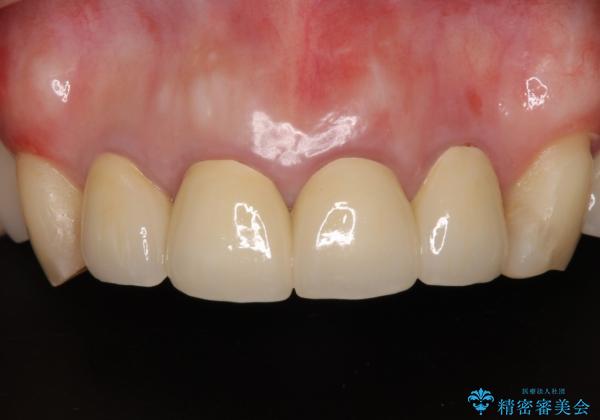

仮歯のまま放置した前歯 オールセラミッククラウンで自然な前歯に

- 仮歯装着後に放置してしまい、恥ずかしいとのことで来院された患者様です。

仮歯が不適合で歯肉が腫脹していたため、しっかりと調整した新しい仮歯にして腫れを改善した上で、オールセラミッククラウンにて補綴することとしました。

日頃の歯磨きをしっかりと行ってくださるので、新しい仮歯に変えてから速やかに歯肉の状態が改善されました。

歯肉からの出血がほとんどないため精度の良い型取りができ、非常に適合の良い補綴治療を行うことができました。